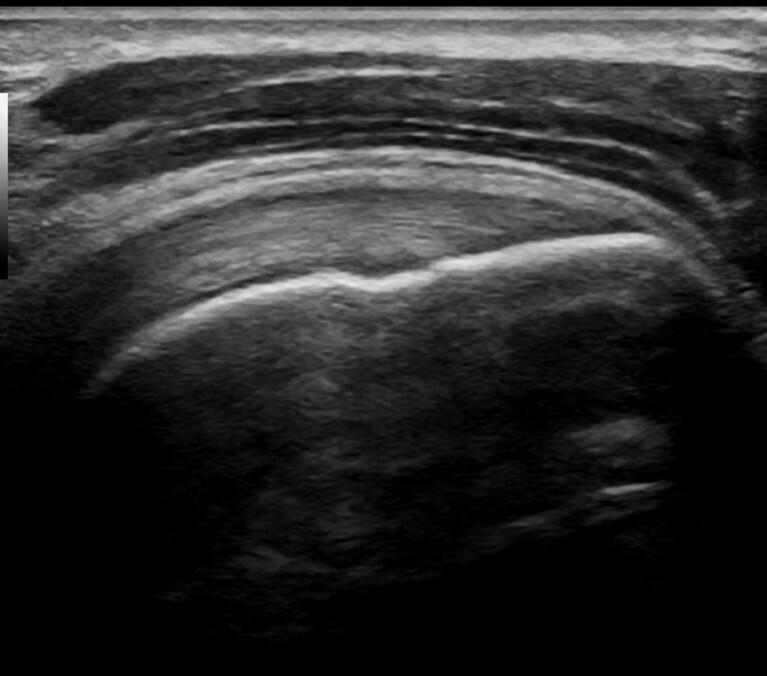

MSK Ultrasound Hands-On Training

Diagnostic Musculoskeletal Ultrasound

1- Day Hands-On MSK US Training

Beginner's Upper & Lower Extremity Course